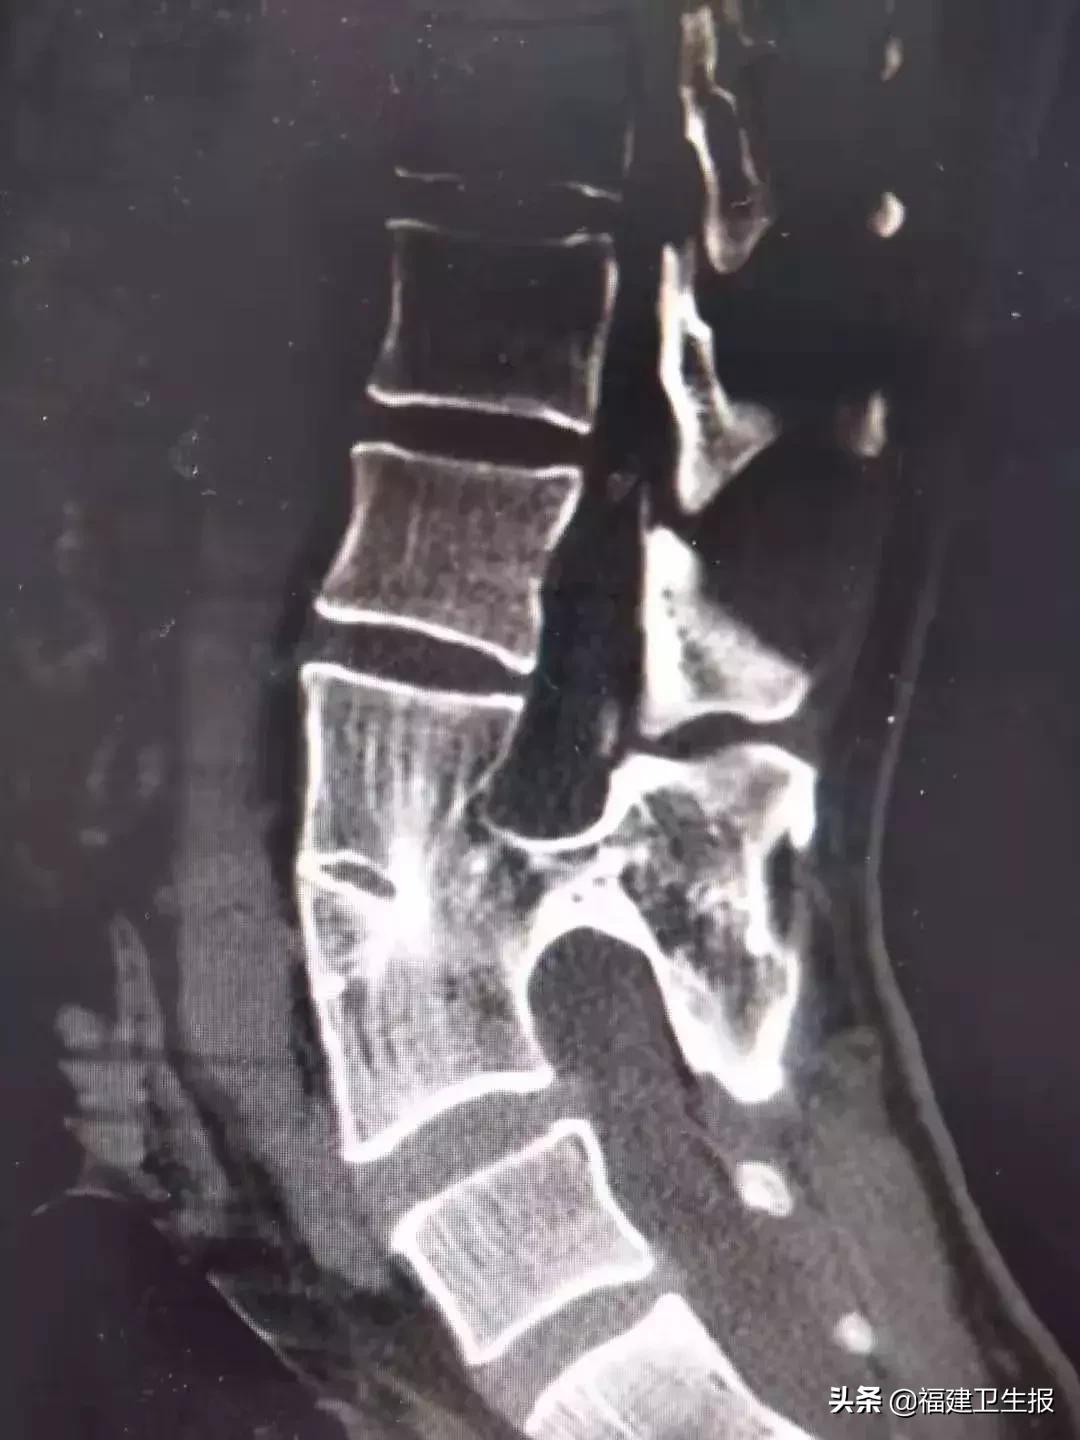

通过CT和MR检查,清晰发现小郭不仅患有脊髓栓系综合征,同时还合并有脊髓分裂症。

随后,在给小郭的手术中印证了他的看法,术中发现,小郭椎管中的畸形骨片把脊髓分裂成2瓣,并把脊髓神经挤压成薄片状。正常椎管内径约2厘米,骨片已经占据椎管1.3厘米。

3节椎骨畸形、异常骨片导致脊髓分裂

“这一段的脊髓被骨片压迫成扁平状,一旦骨片继续生长甚至完全阻断椎管,患者随时会出现瘫痪症状并无法逆转。”幸得手术及时,小郭术后症状消失,恢复良好,十天左右即出院回家。